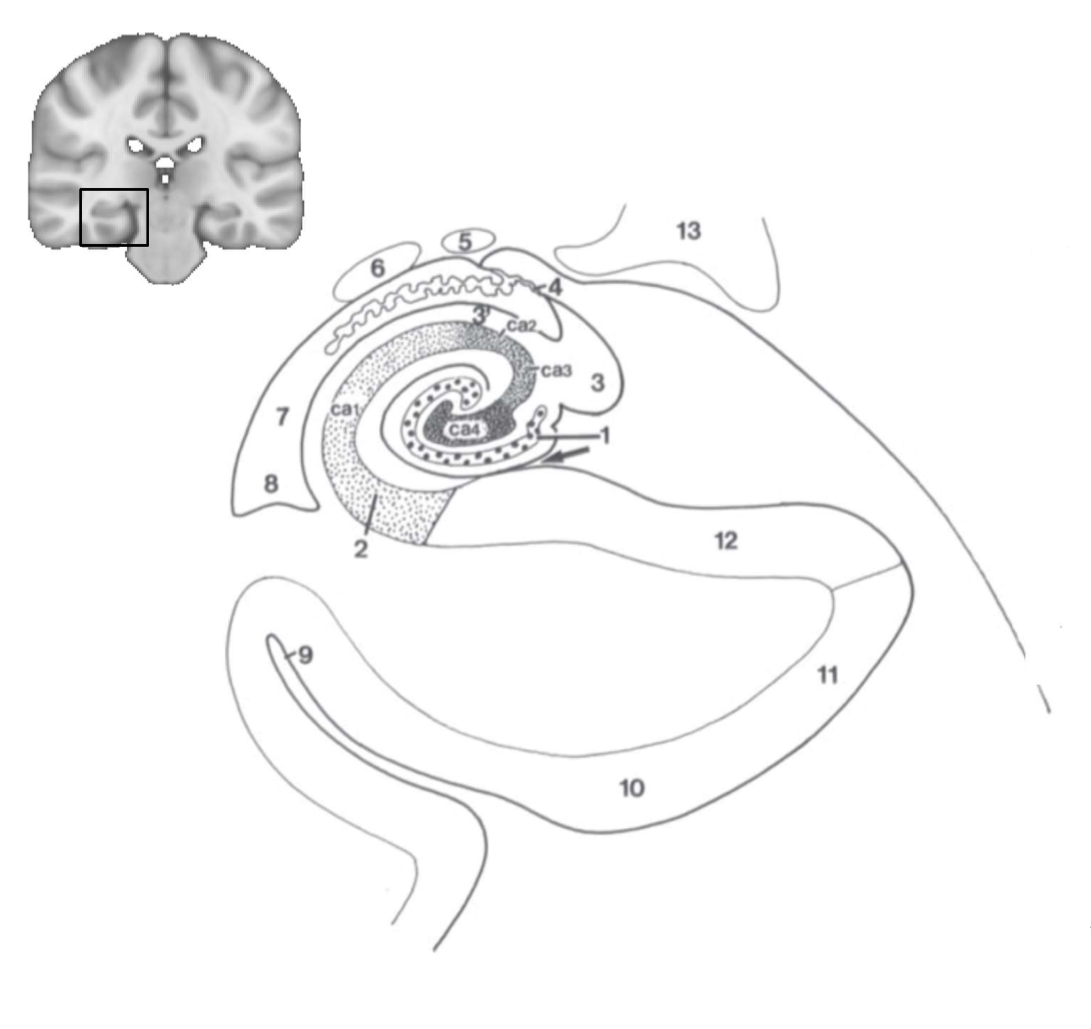

What is 1?

gyrus dentatus

What is 2?

cornu ammonis

What is 3?

fimbria

What is 3’?

alveus

What is the arrow pointing to?

happicampal sulcus

What is ca1, ca2, ca3 and ca4?

fields of cornu ammonis

What is 4?

tela choroidea

What is 5?

stria terminalis

What is 6?

tail of caudate nucleus

What is 7?

temporal horn of lateral ventricle

What is 8?

collateral eminence

What is 9?

collateral sulcus

What is 10?

parahippocampal

What is 11?

entorhinal area

What is 12?

subiculum

What is 13?

lateral geniculate body